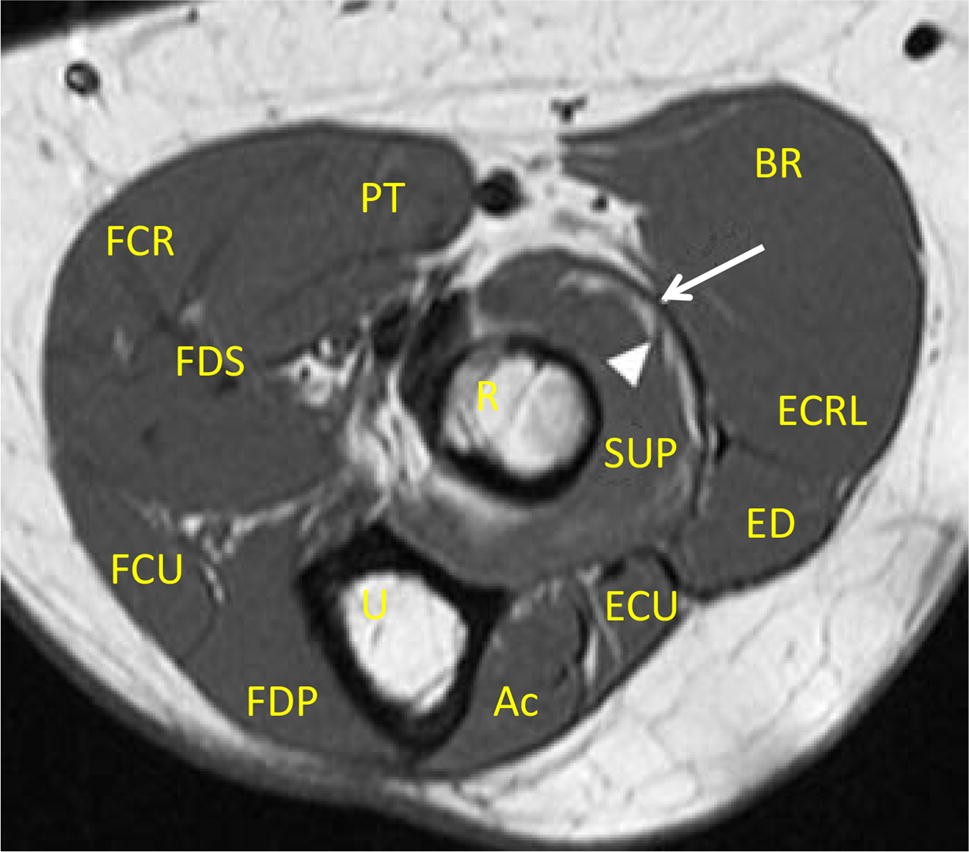

Forearm Muscle Anatomy Mri

Mri Arm Forearm Anatomy Dr Ahmed Eisawy Youtube